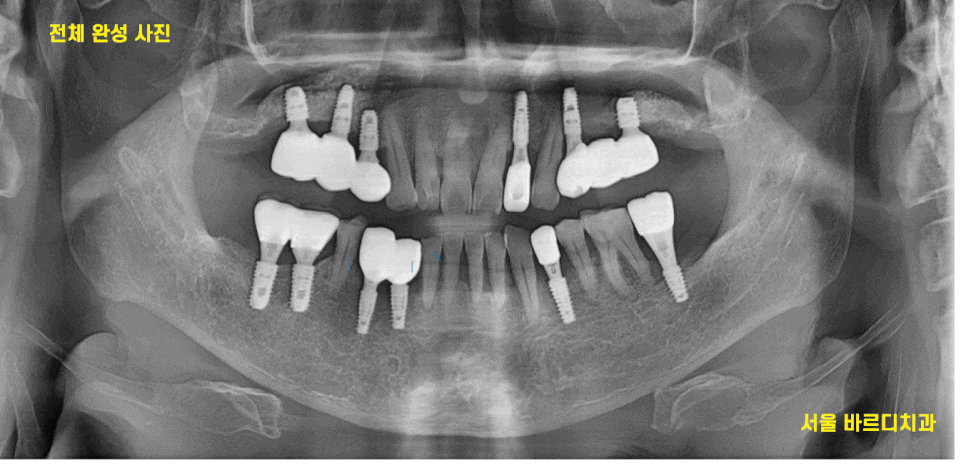

23.11.03

뼈가 좋은 오른쪽 먼저 치아를 완성했습니다.

기존 1개 살린 임플란트와

임플란트 제거 후 재식립한 부분을 연결하여

완성했습니다.

24.01.22

뼈가 약해서 조금 더 기다린 오른쪽도

마저 완성을 한 모습입니다.